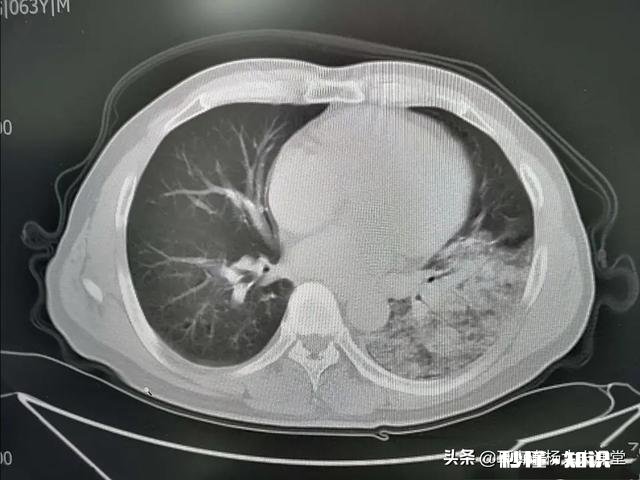

细菌性肺炎和病毒性肺炎影像学表现细菌性肺炎最常见表现为支气管肺炎型改变,CT会显示新出现的斑片状或实变阴影 。如影像肺叶实变、空洞形成或较大量胸腔积液多见于细菌性肺炎 。葡萄球菌肺炎可引起明显的肺组织坏死、肺气囊、肺脓肿和脓胸 。革兰阴性杆菌肺炎常呈下叶支气管肺炎型 , 易形成多发性小脓腔 。